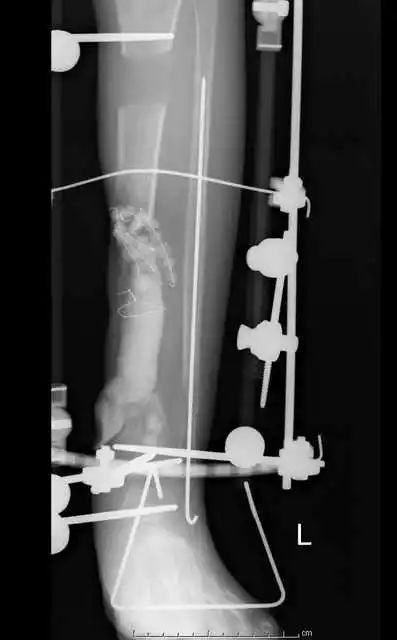

最后一个病例

(网友提供)最后的病例是伤后40天由外地转来。开放骨折外固定架固定,骨坏死外露,用连珠和双氧水冲洗。入院时还存在足下垂,腓神经损伤、胫后动脉损伤。

• 接收该患者后第一次手术  清除病灶去除死骨27cm

• 抗生素骨水泥填塞。远端整块水泥包裹外露骨质,近端连珠以便骨搬移

• 钢丝克氏针张力牵拉皮肤,缩小创面

• 5天后下地部分负重走路

• 联合骨牵引纠正足下垂,5天后足下垂纠正后去除跟骨骨牵引针,保留胫跖骨牵引维持足于功能位。

• 而后行骨搬移、半开放植骨(如下)

• 第一次的骨水泥于80天后去除,行半开放植骨(植骨表面覆盖抗生素骨水泥)

• 因为有皮肤缺损,用骨水泥做成瓦片闭合伤口=半开放植骨

• 自体优质松质骨(如图)

• 皮肤采用了钢丝牵张闭合

• 骨搬移+半开放植骨=治疗缺损

• 植骨后一个月去除瓦片骨水泥,创面新鲜

• 钢丝克氏针张力闭合伤口加游离植皮

• 继续骨搬移

• 入院6个月腓总神经恢复,胫前动脉再通

• 总的治疗过程2年基本完全康复